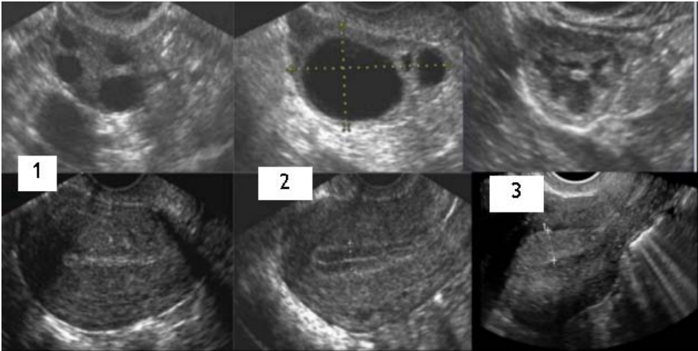

Considere a imagem abaixo:

As figuras 1, 2 e 3 correspondem, respectivamente, a que fase do ciclo ovulatório/menstrual?